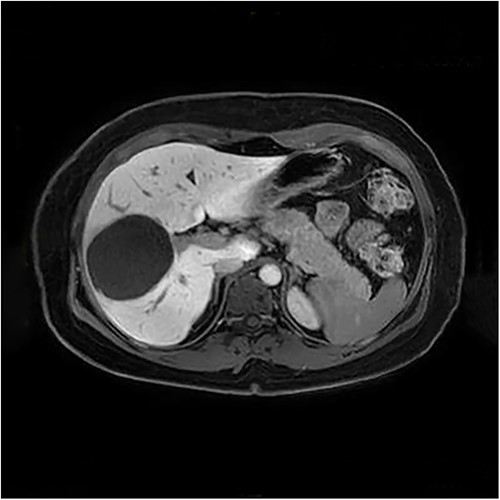

The presenting patient was a 40-year-old Brazilian native who had lived in Europe for ~26 years. Initially, the patient presented to her general practitioner with upper right quadrant pain. An ultrasound study (Fig. 1) showed a small hyperechoic lesion in segment VII measuring ~0.8 × 0.9 cm. Follow-up studies showed an expanding lesion with newer hyperechoic portions. In 2020 a liver specific magnetic resonance imaging (MRI) (Fig. 2) was performed. Here, again, the cyst was expanding, septated and had reached a size of 7.3 × 6 × 6.5 cm. A Echinococcus infection was considered, however, repetitive EIisa for Echinococcus sp./IgG was negative. The alpha protein was 2 ug/L, and well within normal limits. Due to increasing discomfort, an upper gastrointestinal tract endoscopy was performed. Here, gastritis and gastro-intestinal neoplasia could be excluded.

First documentation of liver cyst of the patient in ultrasound.